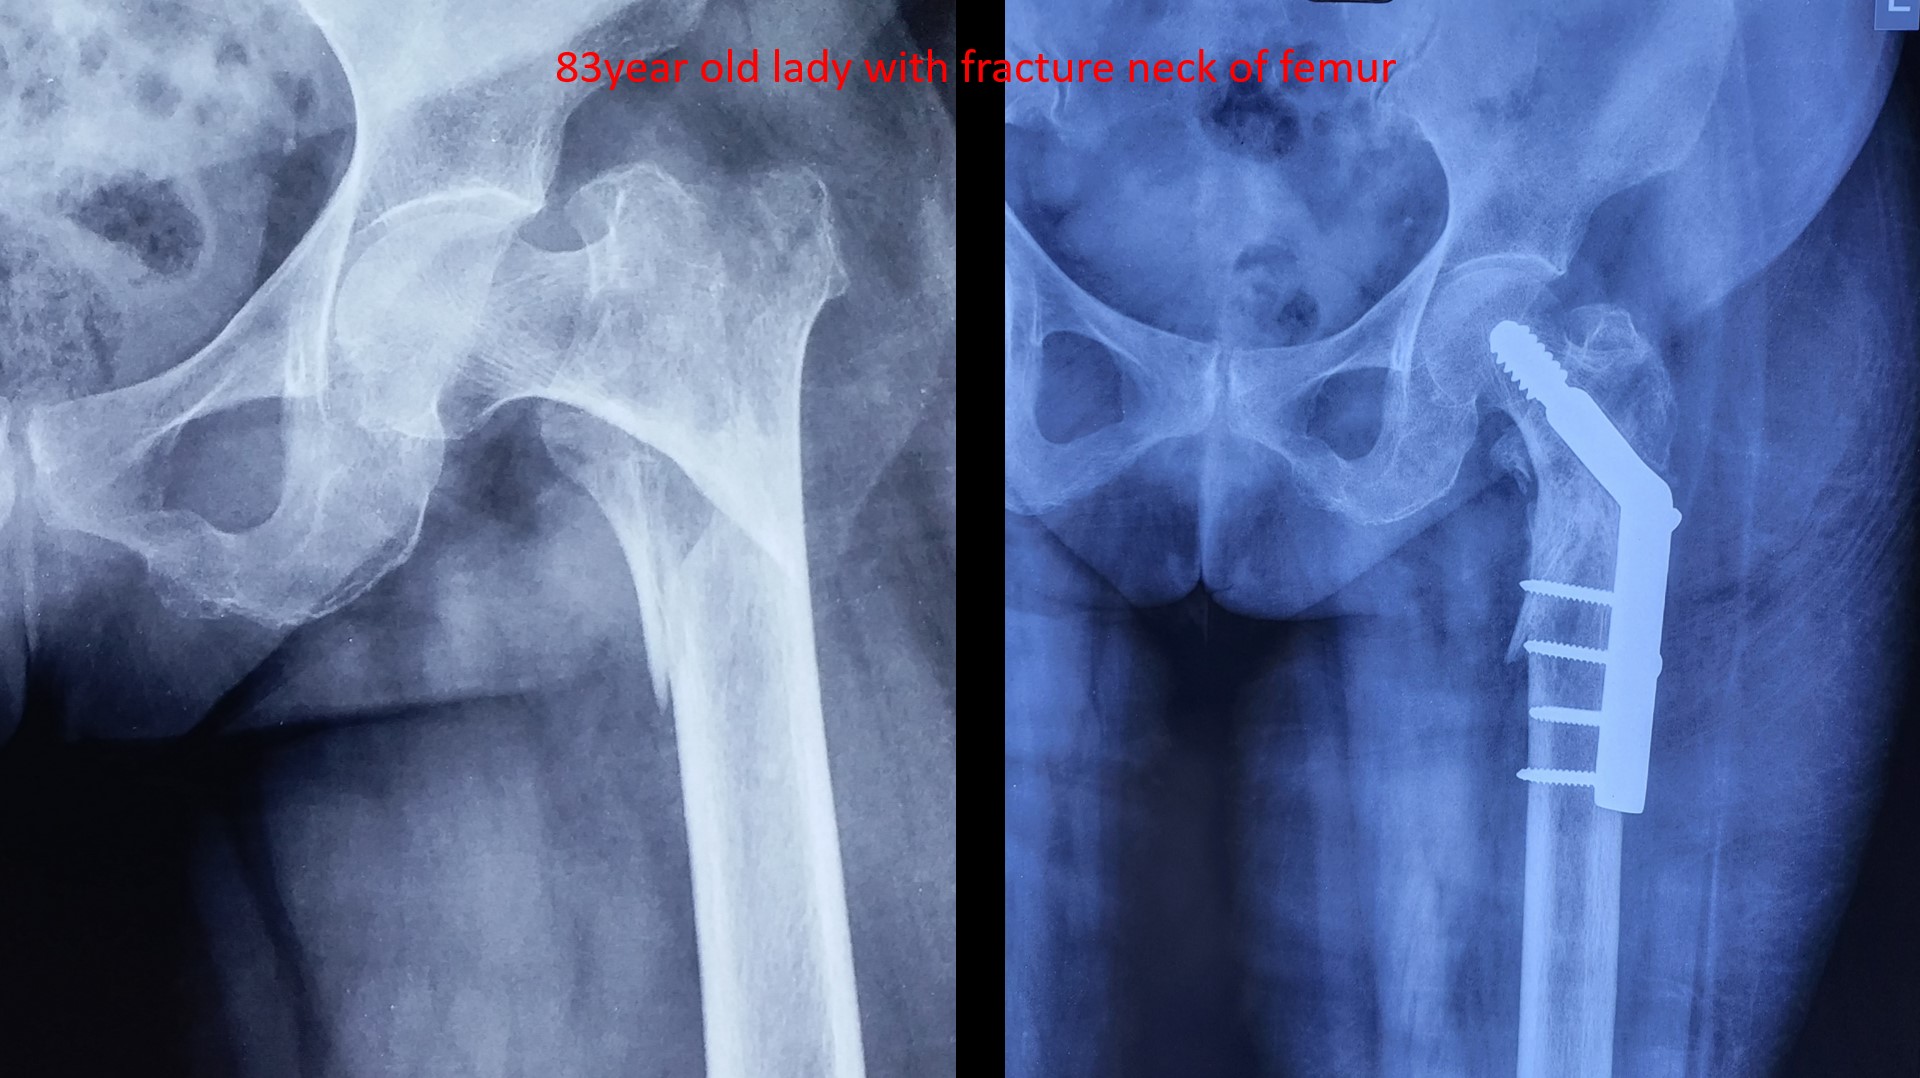

Femer